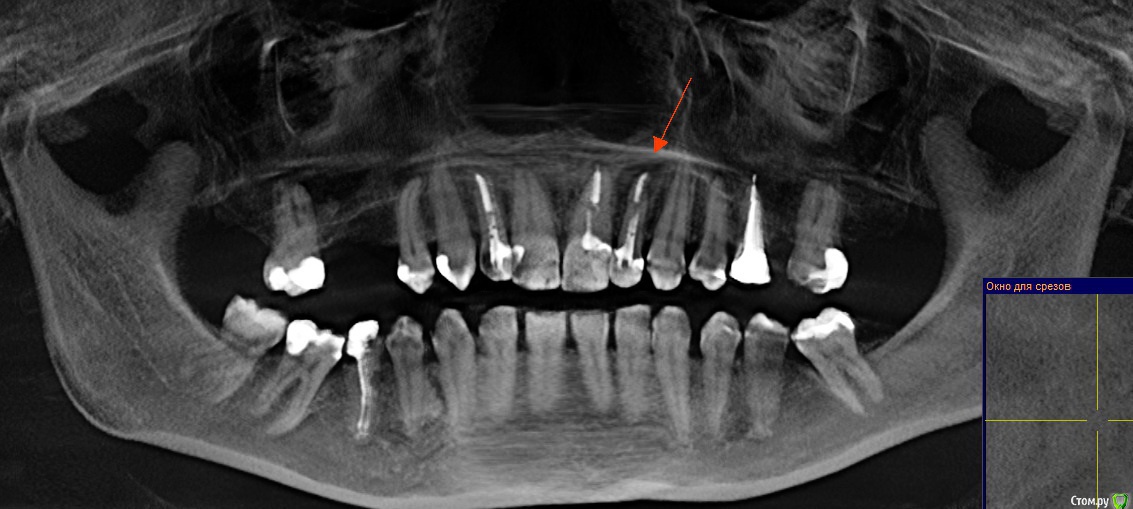

Ankazabolevshaya Опубликовано 28 мая, 2016 Поделиться Опубликовано 28 мая, 2016 Здравствуйте, уважаемые врачи! Очень сильно нуждаюсь в вашей помощи. В 2013 мне лечили два передних зуба (клык и передний). Пломбировали каналы, но коронки не ставили. Этой зимой я почувствовала боль в передних зубах в районе челюсти. Раздражение в дёснах. Резь. Потом вылез какой-то пупырь на десне. Я думала, что это стоматит. Не верила тем, кто мне говорил про нужность обзорного снимка. Признаю свою глупость. Теперь, после КТ оказалось что у меня сломаны эти каналы, а под левым клыком пустота. А пупырь, как мне сказали - это выход свища.Мне предложили зуб удалять. Как-то восстанавливать эту пустоту. Потом делать имплантацию. Есть ли сегодня технологии, позволяющие восстанавливать это пространство под зубом без его удаления, с последующей коронкой на него? И ещё один вопрос: могло ли все это случится из-за какой-нибудь заразы, занесенной во время лечения этих двух зубов в 2013г. ? Так же был момент ранения слизистой левой ноздри, как раз над свищем, который на десне. Просто очень часто слизистая иссыхала в одном месте и я травмировала слизистую. Буду очень благодарна за ответ. От меня в клинике ждут решения, а я переживаю, что улыбка испортится с искусственным зубом. Зуб этот свой очень люблю. Анна. Ссылка на комментарий

red_butler Опубликовано 28 мая, 2016 Поделиться Опубликовано 28 мая, 2016 Спасибо! Можете пояснить, Вы думаете, что зуб можно спасти? если судить только по снимкам, то да 1 Ссылка на комментарий

red_butler Опубликовано 29 мая, 2016 Поделиться Опубликовано 29 мая, 2016 а скажите, как по Вашему, это киста прикорневая? Или челюсть разрушена? Нужно восстановление челюсти? это не важно и корень ведь сломан, поставить под коронки всё равно можно? перелома не увидел И еще последнее, как Вы относитесь к процедуре - депофорез? В моём случае стоит в эту торону смотреть? бесполезно 2 Ссылка на комментарий

red_butler Опубликовано 29 мая, 2016 Поделиться Опубликовано 29 мая, 2016 Как же доказать им что нет на самом деле этого перелома (или корневого канала)? Мы видим только часть срезов Кт, а доктора на очном осмотре и ситуацию в полости рта.Сходите еще на пару консультаций. Как по-вашему – скорее всего виноват тот врач (как раз это тот врач, который настаивает на удалении и на переломе канала), который пломбировал каналы этого зуба в 2013? Или я? Сколько по времени такая штука на корне в среднем формируется? Было и ранение слизистой носа было так же ранение десны во время читки нитью, глубокое и долго заживало. Теперь уже не разобраться, виноват ли врач? Вы не правильно понимаете цели форума, Мы отвечаем на вопросы "что делать" Да и раз депофорез бесполезен, то что с Вашей точки зрения предпочтительнее сегодня в моём случае? Лазер или иссечение корня? Повторное лечение корневого канала. 3 Ссылка на комментарий

Ankazabolevshaya Опубликовано 31 мая, 2016 Автор Поделиться Опубликовано 31 мая, 2016 Всем спасибо большое! Да, так и оказалось, что трещины нет. Отправляла снимки в пару Московских клиник и сходила к эндодантисту , который работает на микроскопе. Через канал всё промыли и заложили лекарство. В извлеченном материале из канала были какие-то чёрные включения. Т.е. пломбирование было не герметичным. Как мне сказали, 70% что заживёт. Если нет, тогда будут иссякать корень. И только если это не поможет, будет удаление. 1 Ссылка на комментарий